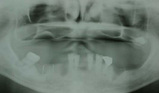

治療前

クリックすると拡大されます

治療後

このことは、文章で説明するよりも症例を見ていただいた方が分かりやすいので、

以下を御覧になって下さい。